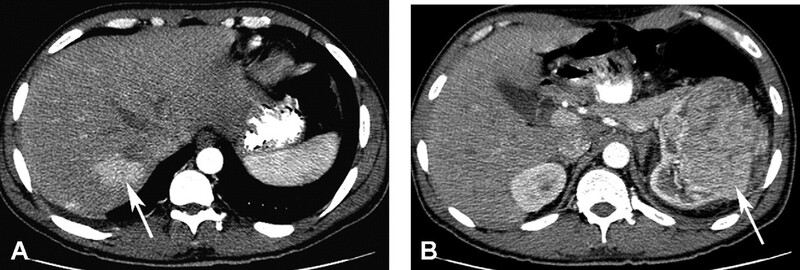

Adenoma tế bào gan (Hepatocellular Adenoma – HCA) là u lành tính có nguồn gốc biểu mô, gặp ưu thế ở phụ nữ trẻ liên quan với uống thuốc ngừa thai. Các liên quan hiếm đã được gợi ý là steroid đồng hóa ngoại sinh, tăng galactose máu và bệnh lý ứ đọng glycogen type Ia. Các khối lớn hơn, thườn gđường kính > 4-5cm, có thể có đau bụng do xuất huyết tự phát. Adenoma gan gồm các lá tế bào gan và hình thành giả bao do ép nhu mô gan kế cận; tuy nhiên, ngược với FNH, chúng không hình thành ống mật. HCA là khối giàu echo, giới hạn rõ trên siêu âm. Tăng echo là do hoặc mỡ bên trong tổn thương hoặc xuất huyết. Các xuất huyết cũ dẫn đến hình ảnh giảm echo hoặc nang, echo trống. Hình CT không cản quang có thể thấy khối giảm đậ độ do sự hiện diện của mỡ hoặc hoại tử. Các vùng tăng đậm độ có thể thấy trong khối do xuất huyết. CT cản quang có thể thấy bắt quang mạnh thoáng qua trong các phần sống của u ở thì động mạch, sau đó thải thuốc nhanh ở thì tĩnh mạch cửa (Hình 8).

Hình 8. Nữ 38 tuổi có sử dụng thuốc ngừa thai đường uống, với adenoma gan vỡ và máu tụ dưới bao. CT không cản quang (A) thấy xuất huyết nội (mũi tên đen) bên trong adenoma và máu tụ dưới bao (mũi tên trắng). Thìđộng mạch (B) thấy bắt quang (mũi tên) phần đặc, thải thuốc và trở nên đồng đậm độ với gan ở thì tĩnh mạch cửa (C). Có vỡ u (mũi tên) ở phía ngoại vi với máu tụ dưới bao.